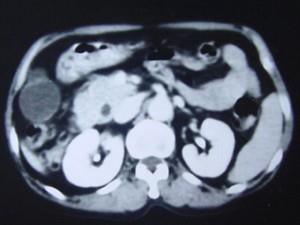

问题 男,55岁,中上腹隐痛多年,剑突下压痛,影像检查如图,最可能的诊断是 ( )

选项 A、十二指肠重复畸形 B、十二指肠穿孔 C、十二指肠憩室 D、十二指肠癌 E、十二肠溃疡

答案 C